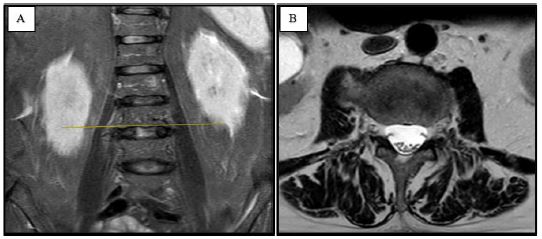

The patient was discharged at home on the second day after the operation. He reported complete relief of pain immediately after the procedure, and at the 6-week follow-up, he was still pain-free. A lumbar computed tomography revealing the absence of the osteophyte was performed 6 weeks after the operation (Figure 4A).

Figure 4: The follow-up lumbar computed tomography, 6 weeks after the operation revealing the absence of the osteophyte: coronal (A) and axial planes (B).